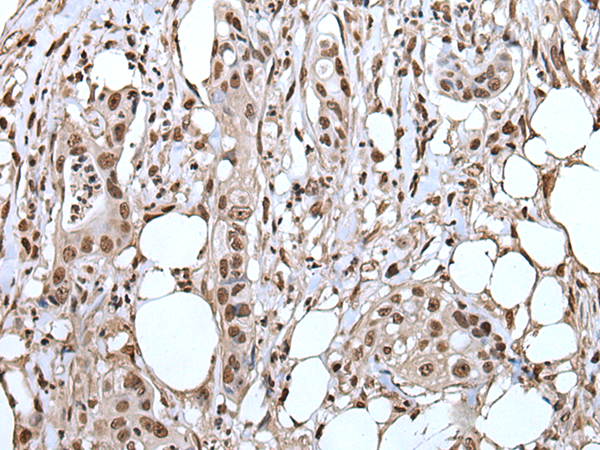

IHC positive control: |

Human colorectal cancer and human cervical cancer |